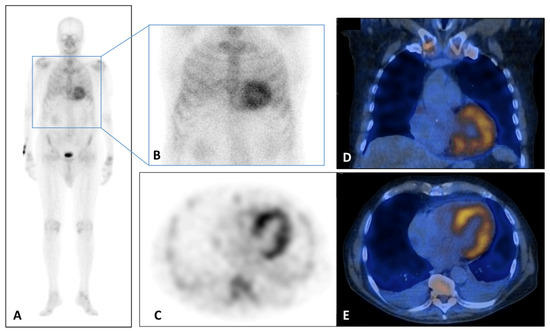

Cardiac ATTR amyloidosis can be diagnosed even without histological confirmation when typical echocardiographic/CMR findings (Table 2 and Table 3) are present along with scintigraphy using bone radiotracers such as 99mTc-pyrophosphate (PYP), 99mTc-3,3-diphosphono-1,2-propanodicarboxylic acid (DPD) or 99mTc-hydroxymethylene diphosphonate (HMDP) demonstrating grade 2 or 3 myocardial uptake; grade 0 stands for absence of tracer myocardial uptake and normal bone uptake, grade 1 for lower myocardial uptake than at bone level, grade 2 for similar myocardial and bone uptake and grade 3 when myocardial uptake is greater than bone). Additionally, exclusion of clonal dyscrasia is required through serum free light chain (FLC) assay, serum (SPIE), and urine (UPIE) protein electrophoresis with immunofixation (Figure 1).

Figure 1.

(A–E) 99Tc-Sn-HDP Scintigraphy performed in a 80 years old man with suspicious of cardiac amyloidosis and absent monoclonal protein. He presented to the emergency department for lipothymia and echocardiogram demonstrated signs of infiltrative cardiomyopathy with a LVEF of 40%, global longitudinal LV strain of −18% in absolute value. In addition, laboratory testing was significant for N-terminal pro b-type natriuretic peptide (NT-ProBNP) elevation at 5053 pg/mL (n.v. < 127.4 pg/mL). Whole Body (A) and static (B) planar bone scintigraphy, completed with tomographic imaging SPET (axial, (C)) and hybrid SPET/CT (coronal, (B) and axial, (C)) demonstrated moderate cardiac uptake. It correlated with score 2 of Perugini grading scale (cardiac uptake with intensity similar rib uptake), confirming the TTR amyloidosis diagnosis. LV, left ventricle; LVEF, left ventricular ejection fraction; NT-ProBNP, N-terminal pro b-type natriuretic peptide.

Therefore, in the presence of echocardiographic/CMR findings with grade 2/3 of myocardial scintigraphy uptake in the absence of a clonal abnormality is highly specific to diagnose ATTR cardiac amyloidosis avoiding the need for endomyocardial biopsy. In cases of confirmed ATTR CA, genetic counselling with TTR gene sequencing are recommended to differentiate between ATTRwt and ATTRv forms.